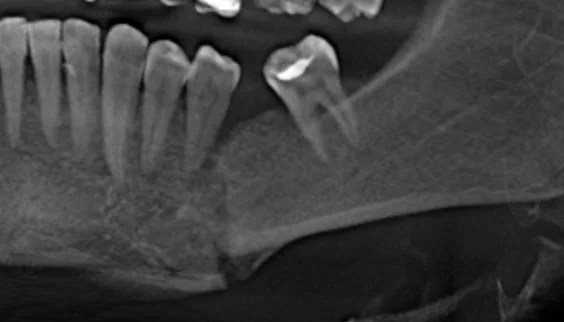

- Удобная программа обработки и просмотра изображения дает четкое понимание о состоянии проблемных зон, качестве и количестве кости, изогнутости корней зубов, анатомических особенностях расположения сосудов и нервов;

- Качественные трёхмерные снимки зубов дают возможность планировать весь процесс стоматологической реабилитации с высокой точностью и минимизировать процент возможных осложнений.

Воссоздавая орган (зуб) или даже совокупность органов, необходимо предельно точно знать исходную ситуацию. Корни зубов, каналы зубов, крупные сосудисто-нервные пучки, идущие внутри костной ткани, верхнечелюстная пазуха во всех подробностях и т.д. - в неискаженном виде все это можно увидеть только на компьютерной томограмме. Стоит ли говорить, что все эти структуры важны для имплантации, так как могут быть легко поврежденфы в ходе операции.

Как получить гарантированный результат имплантации? При помощи компьютерной томографии!